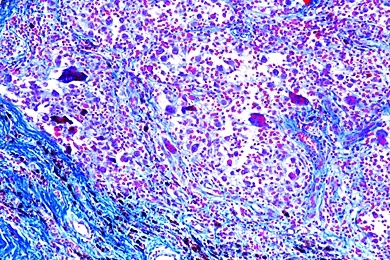

Mikropräparate in Serie - Pathologische Histologie des Menschen, Basisserie, 50 Präparate mit Begleittext

Pathologische Histologie des Menschen, Basisserie 50 Präparate mit ausführlichem Begleittext,

Unsere Mikropräparate werden unter wissenschaftlicher Leitung hergestellt. Sachgemäß fixiertes und konserviertes Ausgangsmaterial ist die Voraussetzung für einwandfreie Präparate. Wir verwenden deshalb auf diese Arbeitsgänge besondere Sorgfalt. Die Herstellung der Mikrotomschnitte erfolgt durch erfahrene Fachkräfte, Schneidetechnik und Schnittdicke werden den Objekten angepaßt. Aus der großen Zahl der in der Mikroskopie üblichen Färbemethoden wählen wir solche, die eine klare und kontrastreiche Darstellung der gewünschten Strukturen mit bester Haltbarkeit verbinden. Meist handelt es sich dabei um Mehrfachfärbungen.